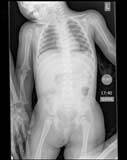

Kiddiegram of a child showing chest and abdomen.